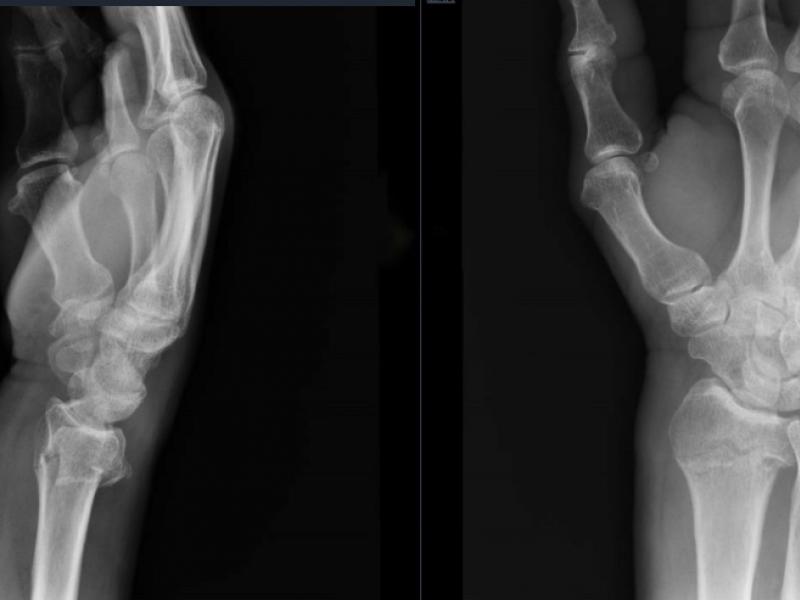

A 57 yo male slipped and fell on ice and presents with right

Critical Cases - Active Gluteal Muscle Internal Hemorrhage!